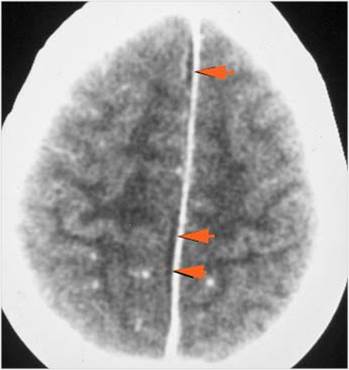

There is brain edema specifically involving the frontal and temporal lobes.

There is cerebritis specifically involving the frontal and temporal lobes.

There is brain abscess specifically involving the frontal and temporal lobes.